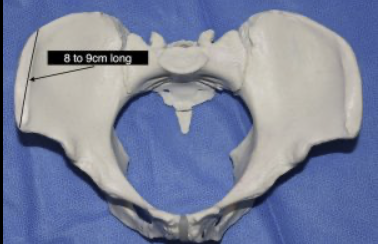

ive been cursed with shitty hips that make it look like im a fatass even while low bf%